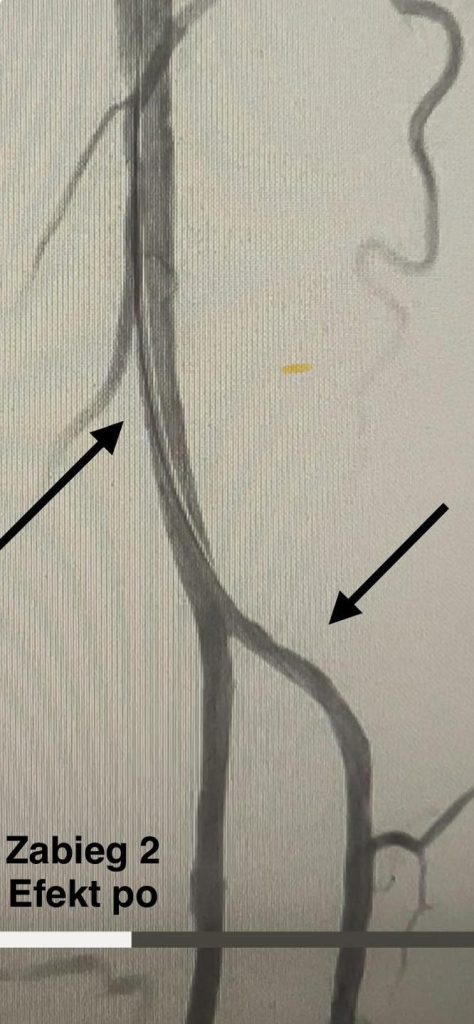

Drugi zabieg przeprowadzono u pacjenta z cukrzycą i przewlekłym niedokrwieniem kończy dolnej. Po amputacji palca u stopy rana nie goiła się prawidłowo. W czasie zabiegu udrożniono tętnicę podkolanową i tętnice podudzia, co poprawiło krążenie. Stan pacjenta po zabiegu był dobry, został wypisany do domu.